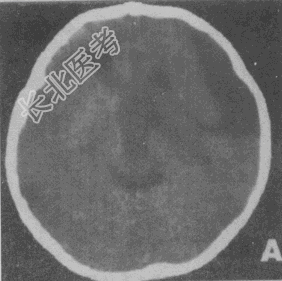

- 单项选择题男性,12岁。智力低下、言语障CT检查如图所不, 请根据CT图像诊断

A、蛛网膜囊肿

B、脑裂畸形

C、Dandy-Wallker综合征

D、囊性胶质瘤

E、左侧侧脑室室间孔闭锁或狭窄